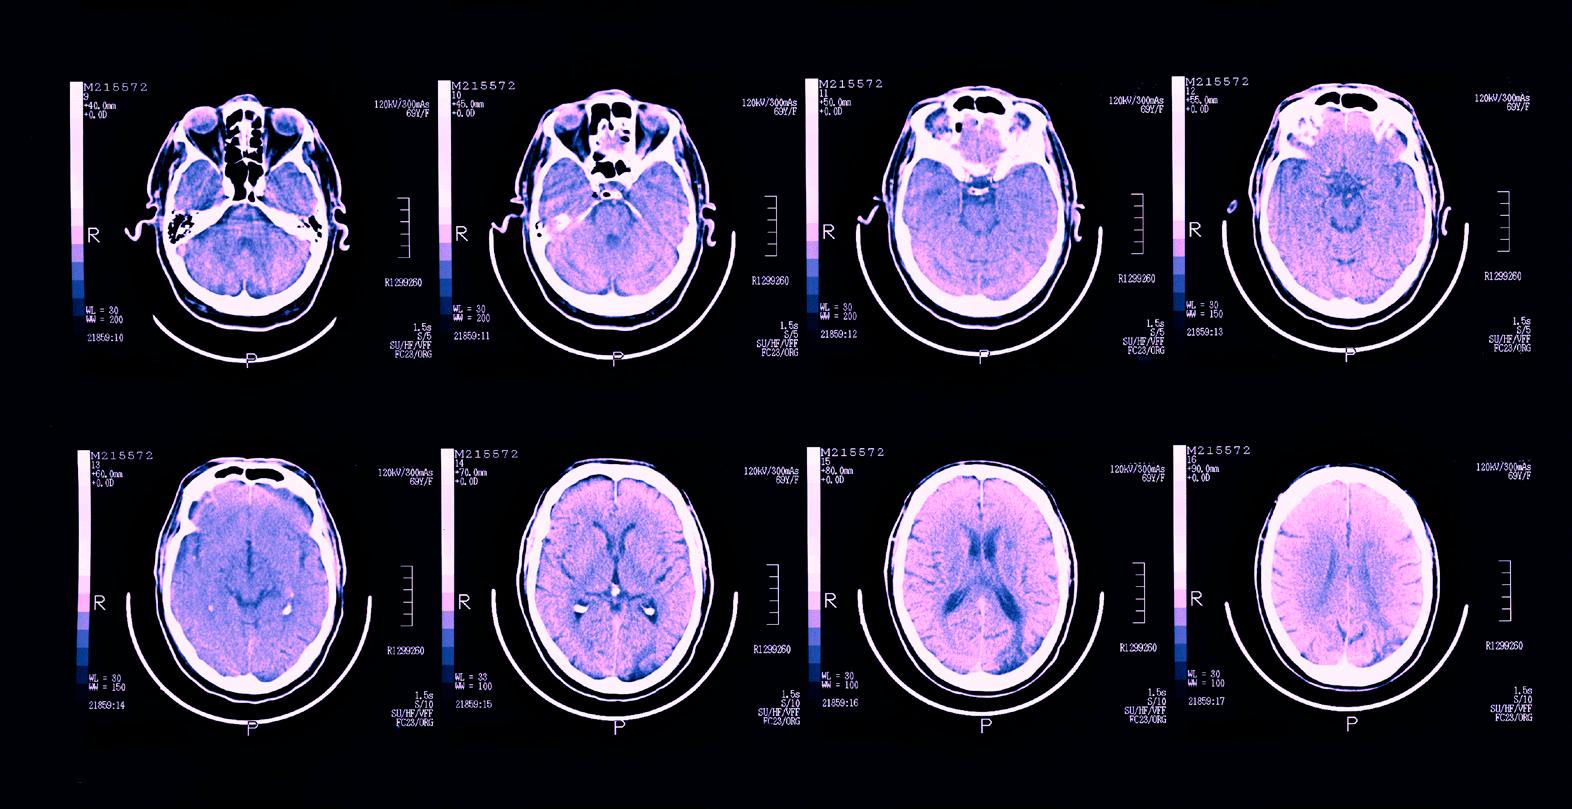

“In recent years, several studies have investigated this heterogeneity using a range of approaches,” Dr. Ivleva says. “MRI studies in schizophrenia have typically utilized case-control designs to identify group-level brain alterations in patient cohorts.”

The findings of these studies have led to the identification of regional gray matter alterations, such as decreased volume, cortical thickness, or surface area in many regions of the brain –but most prominent in frontal and

temporal lobes – as well as widely distributed white matter alterations. While these group-level findings are of interest, Dr. Ivleva explains, the severity and specific features of neuroanatomical alterations vary widely among individual patients.

To better grasp the complexity of the neuroanatomic milieu surrounding psychosis, Dr. Ivleva is employing the B-SNIP biomarker strategies, harnessing the power of MRI along with the clinical biomarkers to identify neurobiologically distinct subtypes within schizophrenia and related disorders. These strategies have the potential to move diagnostic and therapeutic practice away from a reliance on symptom and behavioral features, Dr. Ivleva notes.

Dr. Ivleva adds that neuroimaging is wellpositioned for biomarker development in schizophrenic psychosis, explaining that it could capture phenotypic variations in molecular and cellular disease targets, or in the brain circuits themselves.

In a recent study, Dr. Ivleva and colleagues examined cortical (surface area, cortical thickness) and subcortical (volume) morphology in a cohort of acutely ill patients with never-treated first-episode schizophrenia and clinically stable chronic patients with midcourse schizophrenia. The researchers matched each of these cohorts with a healthy control group.

In the study, gray matter was selected as the subgrouping feature because it consists of neuronal cell bodies, neuropil, glial cells, and synapses and is well documented to be altered in patients with schizophrenia. In addition, the novel DPC algorithm was used to classify individuals with schizophrenia into subgroups with distinct neuroanatomical features.

After analyzing the data, Dr. Ivleva and her colleagues successfully identified three subgroups of patients, defined by distinct patterns of regional cortical and subcortical morphometric features. Interestingly, a similar threesubgroup pattern was identified in the independent dataset of patients from the multisite B-SNIP consortium.

“Similarities of classification patterns across our two patient cohorts indicate the three-group typology is relatively stable over the course of illness,” Dr. Ivleva explains. “These findings provide new clues into distinct subgroups of patients with psychosis based on structural brain features.”

Based on these results, Dr. Ivleva believes that anatomic magnetic resonance subgrouping – along with other cognition, EEG, and eye-tracking biomarkers – may be able to be leveraged to separate neurobiologically distinct subgroups of individuals with psychosis. This represents an important step toward differentiating subtypes of psychotic disorders for understanding and treating the disorder.